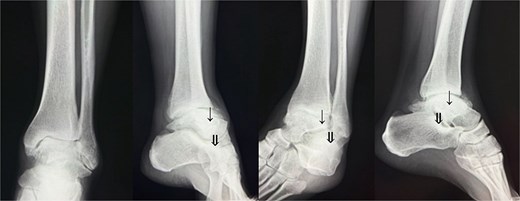

Preoperative radiographs and computed tomography (CT) demonstrated complete loss of the tibiotalar joint space, talar subluxation, and extensive osteophyte formation consistent with end-stage post-traumatic osteoarthritis (Figs 1 and 2). After informed consent and institutional review board approval (IRB number #20251001), the patient underwent arthroscopic ankle arthrodesis.

Preoperative radiological imaging: X-ray finding. The patient presented with end-stage osteoarthritis of the tibiotalar joint, characterized by flattening of the joint surface and subluxation of the talus (↓). Although mild arthritic changes were observed in the subtalar joint (⇓), its articular surface remained preserved.